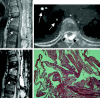

Fig 1.

Case 1. A, Sagittal reconstructed CT scan performed same day as vertebroplasty shows postvertebroplasty appearance with hyperattenuated bone cement in T8, T10, and L1 vertebral bodies. Bone cement filled the anterior vertebral body, the posterior vertebral body, and the epidural space (arrows). The technical flaw in this case was allowing the bone cement to fill the posterior vertebral body and continue filling in the spinal canal. B, Axial view at T7/T8 disk level performed same day as vertebroplasty shows bone cement in the epidural space (black arrows) and pulmonary arteries (white arrows). C, T2-weighted MR imaging performed 50 days after vertebroplasty shows low-signal-intensity bone cement inside the anterior and posterior aspects of T8, T10, and L1 vertebral bodies (white arrows) and postlaminectomy appearance with bloody fluid collection (white arrowheads) causing posterior epidural compression to the spinal cord. There is high-signal- intensity change in the spinal cord on the T2-weighted images, because of compressive myelopathy or previous thermal injury. The posterior epidural compression and signal intensity change of the spinal cord are similar to the MR imaging performed 5 days after the second decompressive surgery. These changes were not present on MR imaging performed 2 days before vertebroplasty. D, Fibrosis of arachnoid membrane (H&E stain).